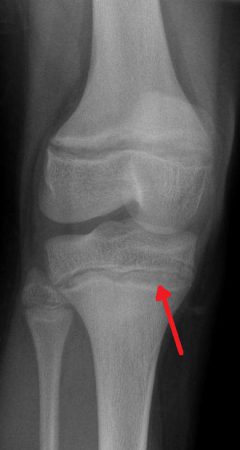

Zagęszczone (sklerotyczne) linie przynasadowe spowodowane zatruciem ołowiem |